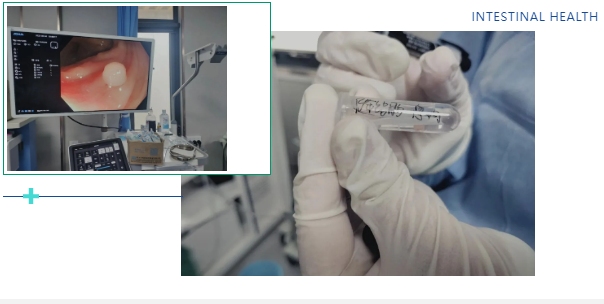

经无痛肠镜检查,吕主任发现李阿姨脾区肠壁增厚,肠道已经出现狭窄,肠镜无法顺利通过。随后取肿物进行活检,最终确诊为结肠癌。这个结果给李阿姨和她的家人敲响了警钟,也让我们深刻意识到,肠道发出的一些看似不起眼的信号,可能隐藏着致命的危机。

肠镜插入与观察:待患者进入睡眠状态后,医生会将带有摄像头的肠镜从肛门缓缓插入肠道,通过肠道蠕动逐步推进。在插入过程中,医生会不断注入少量空气,使肠道扩张,以便清晰地观察肠道黏膜的情况。肠镜上的摄像头会将肠道内部的画面实时传输到显示器上,医生可以仔细查看肠道内是否有息肉、炎症、溃疡、肿瘤等病变。如果发现可疑病变,医生还可以通过肠镜上的活检通道取少量组织进行病理检查,以明确病变的性质。